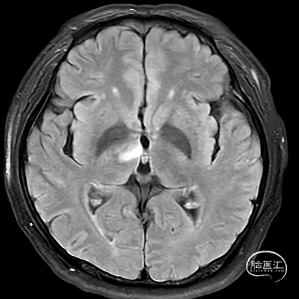

术后即刻复查:远端血管通畅、支架打开良好。

术后正位复查

出院前复查

出院查体:神志清楚,GCS评分=E4V5M6=15分,检查合作,对答反应尚可,头颅五官无明显畸形,双侧瞳孔等大等圆,直径约3mm,双侧瞳孔光反射灵敏。双侧鼻唇沟对称,口角稍左偏,伸舌往右,双侧听力粗测正。右侧肢体肌力5级,肌张力正常,左侧下肢肌力3级,左上肢肌力2级,肌张力正常。双侧腱反射存在,生理反射灵敏,未引出克氏、布氏、巴氏征。